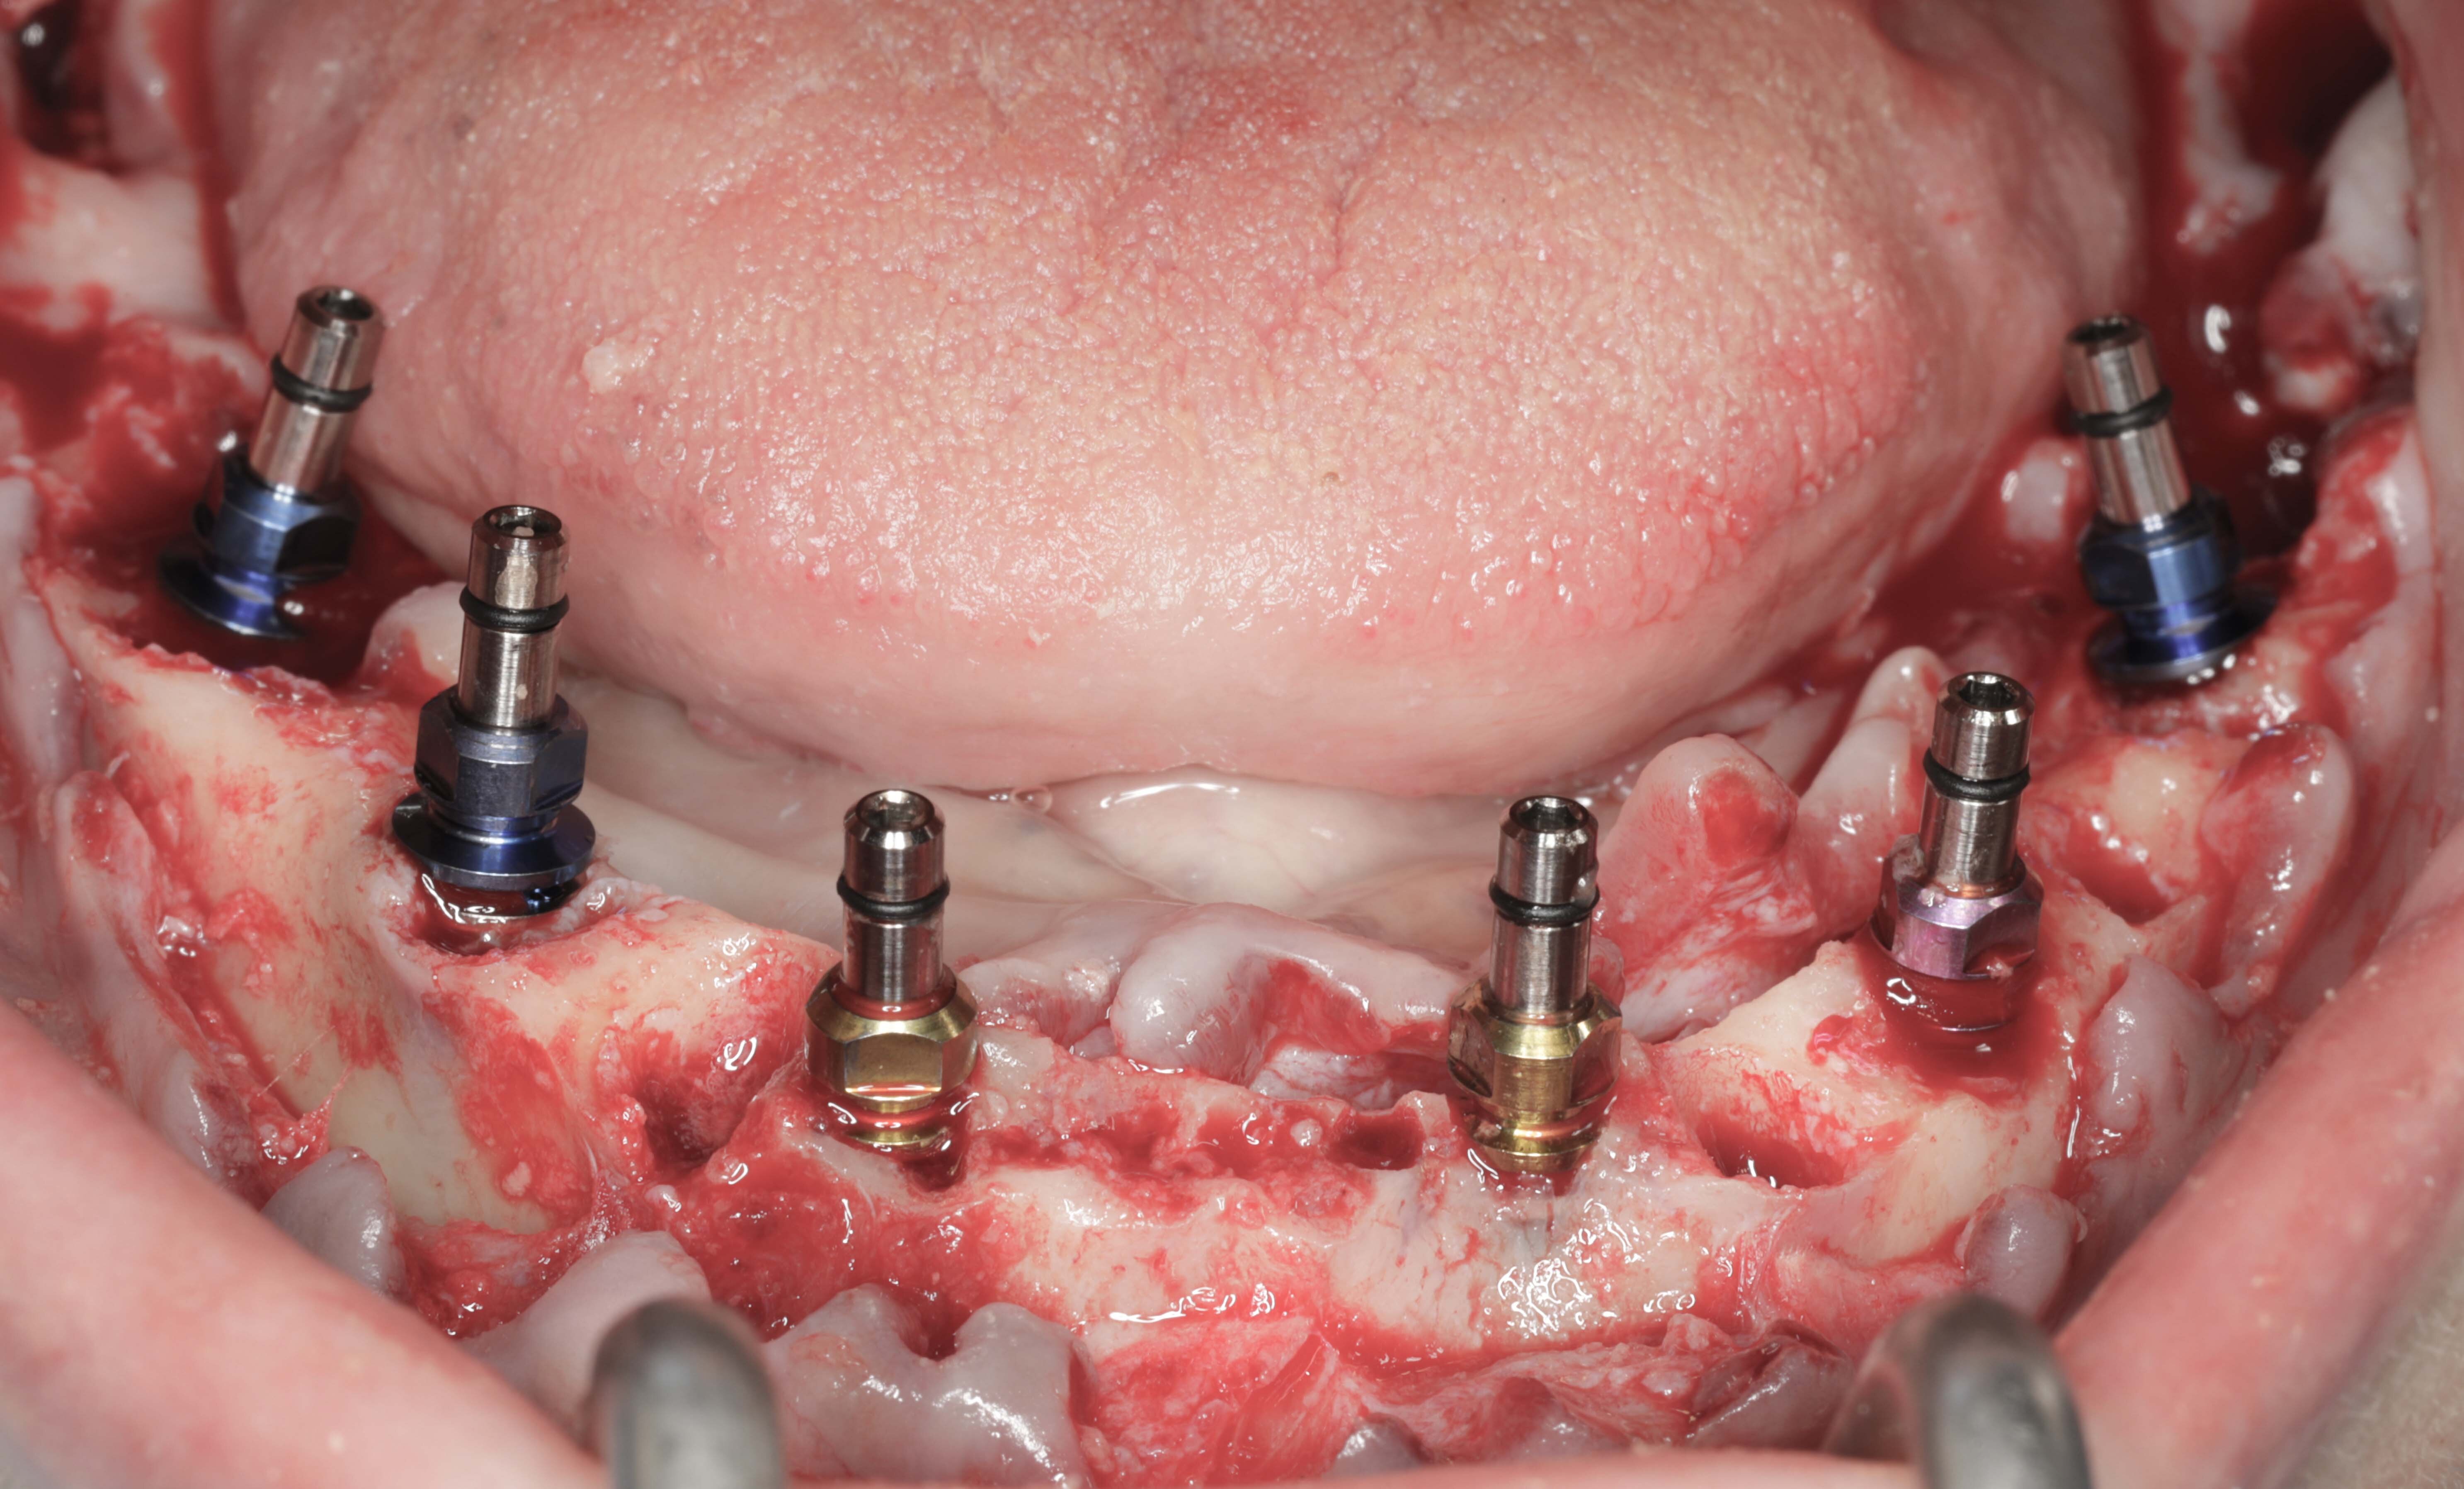

近10年,随着种植体设计和修复部件的技术更新,种植体支持的固定义齿用得越来越多。种植体支持的固定义齿5年成功率89%-100%,其中上颌为81%-100%,下颌为95-100%。

拔除下颌余留牙

拔牙同时植入6颗种植体

手术当天戴入固定临时义齿

6个月后戴入永久修复体